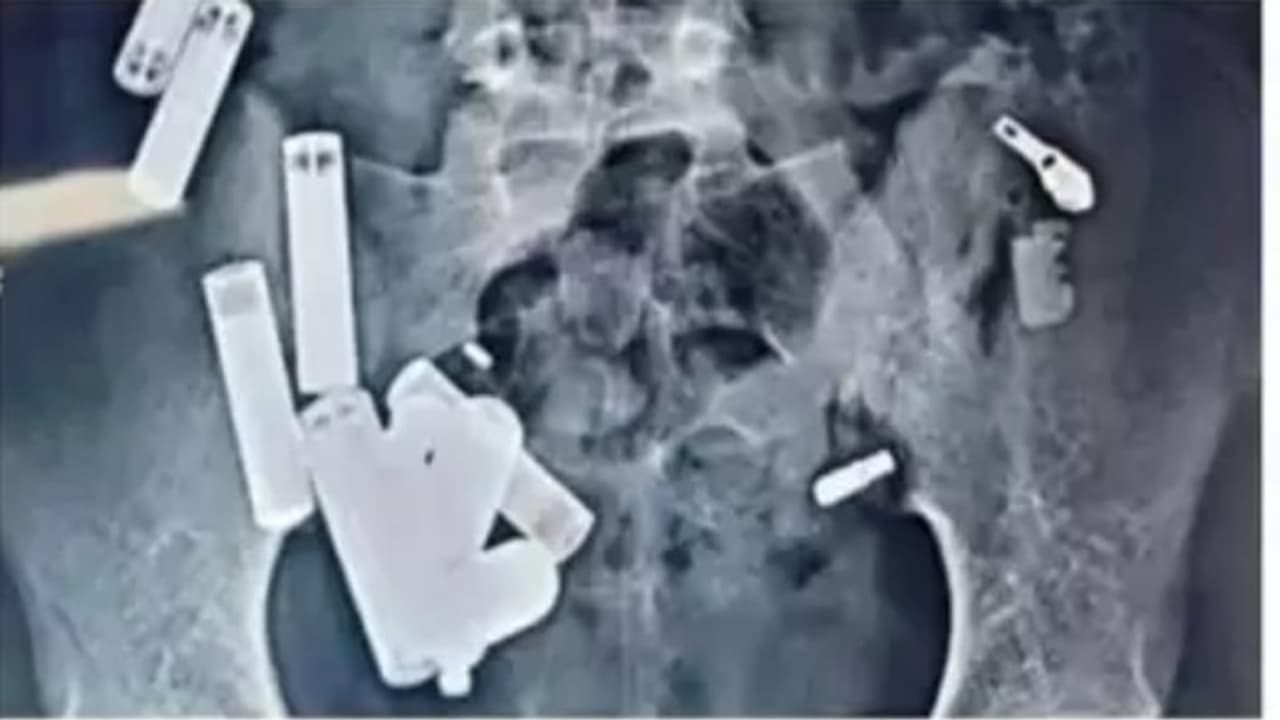

हाथरसच्या १४ वर्षीय आदित्य शर्माच्या पोटातून डॉक्टरांनी पाच तासांच्या शस्त्रक्रियेत बॅटरी, साखळी, रेझर, ब्लेडचे तुकडे आणि स्क्रू यासह ६५ वस्तू काढल्या. मात्र, शस्त्रक्रियेनंतरही संसर्गाने त्याचा मृत्यू झाला.

आग्रा. उत्तर प्रदेशातील हाथरस येथील १४ वर्षीय आदित्य शर्माचा दुःखद मृत्यू सर्वांना हादरवून टाकणारा आहे. दिल्लीतील सफदरजंग रुग्णालयात डॉक्टरांनी आदित्यच्या पोटातून पाच तासांच्या गुंतागुंतीच्या शस्त्रक्रियेत बॅटरी, साखळी, रेझर, ब्लेडचे तुकडे आणि स्क्रू यासह ६५ वस्तू काढल्या. मात्र, शस्त्रक्रियेनंतरही डॉक्टर त्याला वाचवू शकले नाहीत आणि संसर्गाने त्याचा मृत्यू झाला.

नोएडामध्ये डॉक्टरांनी तपासणी दरम्यान त्याच्या पोटात आणखी ४२ वस्तू आढळल्या, ज्यामुळे त्याला तातडीने दिल्लीतील सफदरजंग रुग्णालयात नेण्यात आले. तिथे डॉक्टरांना स्कॅनमध्ये "एकूण ६५ वस्तू" आढळल्या आणि या स्थितीत त्याची हृदयाची गती प्रति मिनिट २८० पर्यंत पोहोचली होती. पाच तासांच्या शस्त्रक्रियेनंतरही डॉक्टर त्याला वाचवू शकले नाहीत आणि त्याचा दुःखद मृत्यू झाला.